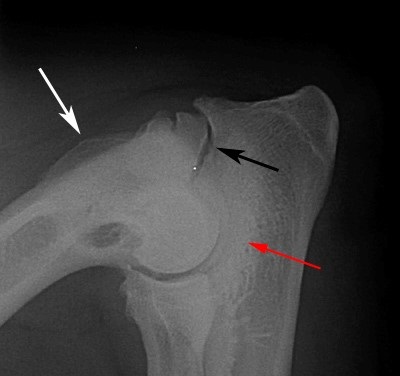

A betegség diagnózisa alapján röntgen vizsgálat. Képek diszplázia könyökízület fut egy egyenes vonal craniocaudalis és oldalvetületbe lateromedialnoy egyidejűleg a képeket a csípő, amikor eléri a 12 hónapos kor. a kis- és közepes méretű fajták és 18 hónap. A nagy és óriás fajták.

Az oldalirányú kiemelkedés mellső láb kell hajlítani a könyök szögben 36-45 °. Ilyen helyzet lehetővé teszi, hogy láthatóvá tegyük a folyamatok minimális zavaró árnyékok.

A - ás porcszövet eredetű exostosisok (kinövések) a condylus humerus;

B - exostosisok a kampó alakú nyúlvány;

B - a porc melletti sclerosis a ker. Vágás után blokk;

G - exostosisok a cranialis része a sugár.

- Nem tünetek (ED -)

- Border formában DLS (ED +/-), ahol van egy zóna fokozott csontsűrűség (porc melletti szklerózis) disztális végénél vagy vágó blokk hooklike folyamatban. Javasoljuk, hogy ismételje meg a tesztet, hat hónap után

- Kisebb arthritis (ED +) 1. fokú. A jelenléte a csontképződés, hogy kevesebb, mint 2 mm, egy vagy több a következő: közös részek: a horog alakú nyúlvány dorsalis, cranialis irányban, hogy a fejét a sugár és a condylusa a humerus és a belső koronoid; jelentős sclerosis blokk ágak

- Az átlagos mértéke (ED ++) 2. fokozat. Bone kinövések értéke 2 és 5 mm-es egy vagy több meghatározott szint 1 mező

- Súlyos ízületi gyulladás (ED +++) harmadik foka. Bone kinövések értéke több, mint 5 mm a talajszint felett